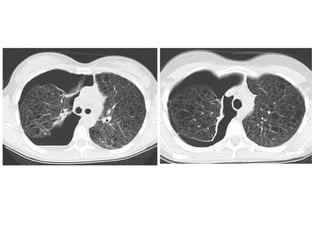

(a) UIP is characterized by heterogeneous lung abnormalities consisting of

subpleural honeycombing (arrowhead), reticular opacities, and traction

bronchiectasis, (b) NSIP demonstrates homogeneous lung involvement with

predominance of ground-glass opacity combined with sub-pleural linear

opacities and micronodules. The microcysts in NSIP (arrowhead) are much

smaller than the honeycombing in UIP